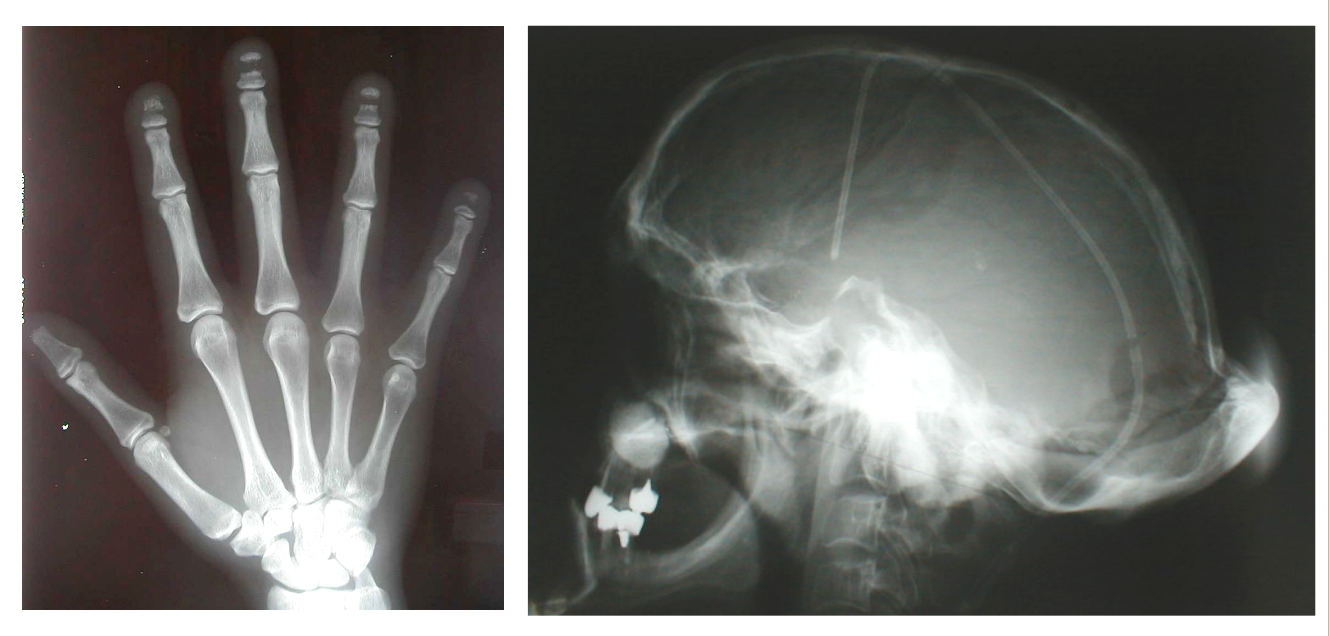

A. Skeletal Abnormalities: HCS is characterized by distinctive skeletal dysplasia. One of the hallmark features is acro-osteolysis—the progressive resorption of the distal (furthest) phalanges (finger bones) , particularly of the fingers and toes. Other skeletal features include:

- X-rays of the hands and feet to evaluate acro-osteolysis.